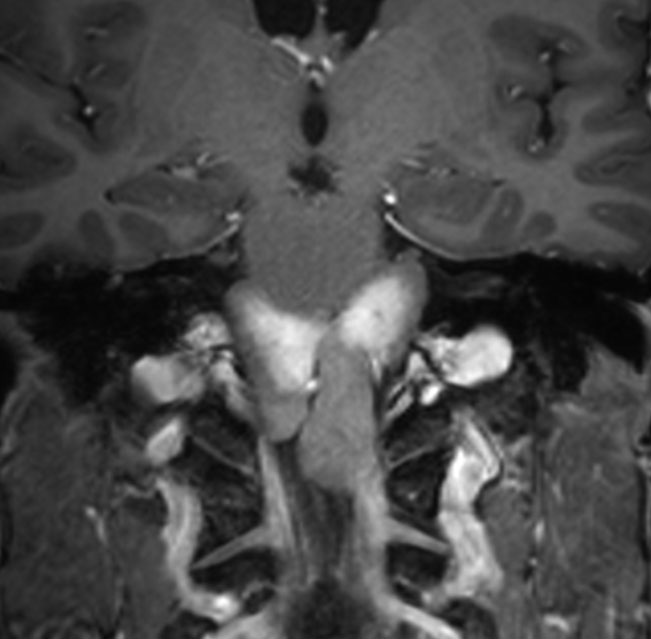

肉芽腫になってしまった第3脳室コロイドのう胞

CTでは壁が厚く高密度,MRI T2強調画像では低信号,T1強調画像では高信号です。内部に血液を含んでいるようなのう胞に見えます。のう胞の壁は非常に厚く硬いものが予想されます。閉塞性水頭症になっています。

若い男性ですが,内視鏡手術では摘出できない壁がガチガチのものでした。モンロー孔が広いので経脳梁到達法 transcallsal approachで手術しました。右前頭部から入ろうとしましたが,架橋静脈のために入れず,左前頭葉を除けて,透明中隔の正中に達しました。ところが,左の脳弓が菲薄化して広がり腫瘍の上面にみえましたから,左のモンロー孔からは摘出できませんでした。しかたがないので,右のモンロー孔から腫瘍を摘出しています。腫瘍の周囲には第3脳室脈絡叢が広範囲に癒着していました。のう胞内容は暗褐色の古い血腫でした。のう胞の壁は硬く厚い結合織で肉芽腫のような肉眼所見でした。左右の脳弓にも癒着し,内大脳静脈にも癒着していたので,その部分には皮膜を残しました。

術後のMRIです。幸い,記憶障害などの脳弓症状はでませんでしたが,かなりリスクの高い手術でした。

のう胞壁の組織像は大部分が線維性に肥厚した結合織膜でした。裂け目のように見えるのはコレステロール choresterol crystalが抜けた部分です。その間に異物巨細胞(黄色の矢印)が多数見られます。のう胞内容が古い血腫でしたから, ヘモジデリンを貪食したマクロファージ (CD68+)が見られ慢性炎症所見です。病理診断としては,コレステロール肉芽腫 chorelsterol granulomaとなります。免疫組織染色でCam5.2陽性の細胞があり扁平ないし立方上皮を形成していました。病理診断では,第3脳室コロイドのう胞が変性消褪して瘢痕化した病変と結論付けられました。